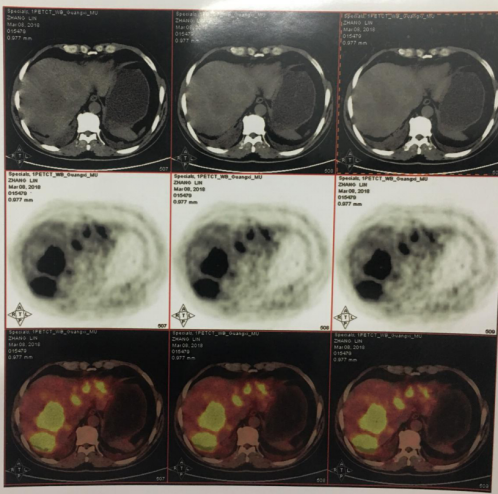

2018-03-08 PET/CT示:胃癌(?)并全身多发淋巴结转移、肝脏多发转移、双肺上叶多发转移;

2018-11-19 PET/CT

胃壁代谢稍增高但未见明确的肿物,肝内低代谢结节考虑转移瘤治疗后活性减低,纵膈及右肺门两个淋巴结代谢增高,考虑转移瘤活性尚存、左侧颞骨局部骨质破坏并代谢增高,考虑转移瘤。